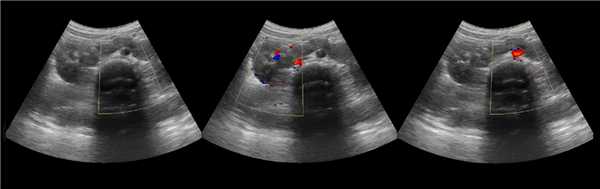

Клинический пример из первой группы. Пациент М., с хронической почечной недостаточностью. Трансплантация почки произведена от живого родственного донора. Трансплантат находится в правой подвздошной области. При нормальном функциональном состоянии трансплантата, показатели цветовой и спектральной допплерографии оценивались как удовлетворительные, с индексом резистентности не более 0,60 (рис. 1); показатели жесткости паренхимы почечного трансплантата при УЭСВ на различных участках составили от 20,05 до 29,18 кПа (рис. 2-4).

Рисунок 1. Ультразвуковое исследование в режиме цветовой и спектральной допплерографии в междольковых и сегментарных артериях у пациента М. Показатели кровотока в данном случае не изменены

Клинический пример из второй группы. Пациент К. перенес операцию пересадки почки от живого родственного донора. Трансплантат в левой подвздошной области. Индекс резистентности в междольковых артериях составил 0,70 (рис. 5). В сегментарных артериях индекс резистентности составил 0,66 (рис. 6). Показатели жесткости паренхимы почечного трансплантата при режиме УЭСВ составили от 31,6 до 36,9 кПа (рис. 7-9).

Рисунок 5. Исследование у пациента К. в режиме цветовой и спектральной допплерографии. Индекс резистентности в междольковых артериях почечного трансплантата составил 0,70

Рисунок 6. Эхограмма пациента К. Кровоток в сегментарных артериях неизменен